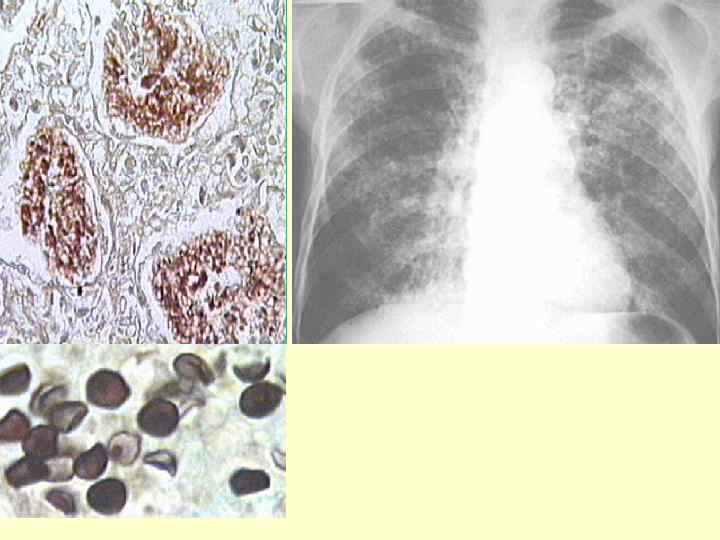

СПИД – индикаторные заболевания Инфекционный процесс при ВИЧ–инфекции очень индивидуален. Больной утрачивает свой иммунитет постепенно и каждой стадии болезни свойственны свои проявления. Вначале у больного возникают «обычные» заболевания, но которые протекают необычно: более длительное течение, необычная локализация патологического процесса, частые рецидивы, чаще сочетанное поражение многих органов и систем одновременно и т. д. Но только при значительном снижении иммунитета (уменьшение количества СД 4 лимфоцитов до 200 в мкл. крови) у больного появляются заболевания, которые у лиц с полноценным иммунитетом не возникают даже при частом инфицировании, что позволило врачам отнести их к СПИД – индикаторам, обнаружив которое врач должен подумать о вероятности ВИЧ у пациента !!!!

Все индикаторные заболевания распределены: 2 1. По локализации пораженного органа: - кожа и слизистые оболочки - лёгкие и верхние дыхательные пути - желудочно-кишечный тракт - периферическая и ЦНС - сердце - глаза - системные ( конституционные) поражения 2. По этиологии: - вирусы - простейшие - бактерии - опухоли - грибы